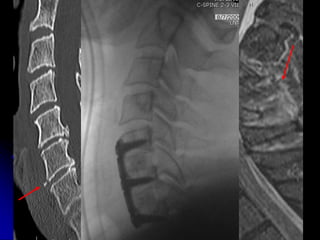

1 2 3 4

WHICH PATIENT HAS ACUTE FX WITH SUBSEQUENT FUSION?

3

T6 T6

L2